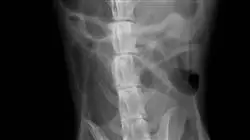

O Curso de Cirurgia Gastrointestinal de Pequenos Animais é um projeto educacional comprometido com a formação de profissionais de alta qualidade. Trata-se de um programa elaborado por profissionais especializados em cada área específica que se deparam diariamente com novos desafios cirúrgicos.

O Curso cobre de forma teórica e prática, através de material multimídia, os aspectos básicos, patologias clínicas e técnicas cirúrgicas mais frequentemente utilizadas em cada parte do trato gastrointestinal, começando com uma revisão anatômica básica, essencial para a formação de um bom cirurgião. Além disso, serão dados conselhos e atualizações que podem ajudar o aprendiz tanto a lidar com complicações como a abordar com sucesso seu trabalho utilizando os procedimentos abordados nesta área.

A revisão sera realizada desde o estômago, intestino delgado, intestino grosso, reto, incluindo intervenções na área perianal e sacos anais. Desta forma, este Curso visa permitir aos alunos aperfeiçoar suas técnicas cirúrgicas, para que possam oferecer um serviço de alta qualidade aos seus pacientes.